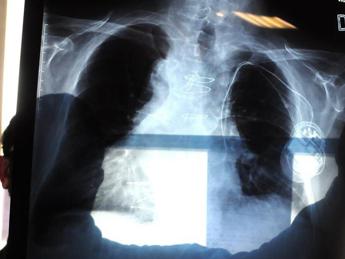

Tumori, Pastorino (Int): “Screening polmonare nei Lea per prevenzione globale”

(Adnkronos) – “La Rete italiana screening polmonare (Risp) sta funzionando  in modo omogeneo. Entro la fine dell’anno porteremo al ministero della Salute i risultati sia in termini di diagnosi che di prevenzione primaria di cessazione del fumo. Crediamo che ci siano gli elementi per prendere una decisione sull’introduzione dello screening polmonare nei Lea (Livelli essenziali di assistenza). Oggi, con un esame semplice, innocuo che richiede pochi secondi, come la tac spirale a basse dosi, possiamo dimostrare il danno globale del forte fumatore e attivare una prevenzione individuale e mirata sul livello di danno. L’analisi con intelligenza artificiale delle calcificazioni coronariche, di chi è entrato in screening 15-20 anni fa, ha permesso infatti di verificare il rischio di mortalità nei 12 anni successivi”. Lo ha detto Ugo Pastorino, direttore della struttura complessa di Chirurgia toracica dell'Istituto nazionale dei tumori di Milano, oggi in audizione in Commissione Affari sociali della Camera sul ‘Piano europeo di lotta al cancro’. ”Il Servizio sanitario inglese – ricorda Pastorino – ha deciso, due settimane fa, di stanziare 250 milioni di sterline per screenare un milione di inglesi. L’Italia è in una condizione molto favorevole e trainante a livello europeo per dimostrare che una scelta di questo tipo può essere fatta anche dai Paesi Ue. E’  una scelta – aggiunge – che sposta parte delle risorse dalla terapia, che assorbe l’80% delle risorse, verso la prevenzione, che ne assorbe meno del 5%, con un guadagno sia in termini di qualità di vita che di risultati, ma anche di riduzione dei costi legati al trattamento della malattia cornica e oncologia avanzata e metastatica, come accade nei tumori polmonari”. Nel raccontare l’esperienza italiana, Pastorino spiega che “l’Istituto tumori di Milano, in particolare, ha realizzato studi che hanno dimostrato che è possibile, non solo ridurre la mortalità da cancro al polmone, ma di fare, con dosi bassissime di radiazione, in base al rischio individuale, lo screening per definire, per ciascuno, il rischio nei 10 anni successivi. Gli studi dell’Int – sottolinea Pastorino – hanno anche dimostrato che usando un farmaco naturale, la citisina, si può far smettere di fumare il 40-50% dei fumatori cronici che fanno screening. C’è quindi la possibilità di una prevenzione globale. Grazie all’intelligenza artificiale (Ai) e ai nuovi programmi applicati su tutti gli esami Tac fatti nei vent’anni precedenti – oltre 10mila volontari e più di 30mila esami – dimostriamo che la Tac del torace può quantificare precisamente il danno cardiaco, dalla misura delle calcificazioni coronariche, e quello polmonare, dalla valutazione delle parti di polmone distrutte dall’enfisema. Questo – chiarisce l’esperto – apre a enormi possibilità di prevenzione in tutti i campi non solo perché si può misurare il danno accumulato, aiutare il paziente e motivarlo a smettere di fumare, ma anche per la possibilità di una diagnosi anticipata di altre patologie che, insieme al cancro del polmone, sono la prima causa di morte nei forti fumatori".  Il Risp è stato finanziato dal ministero “con un progetto che ha selezionato 18 centri sul territorio nazionale, d’intesa con la conferenza Stato-Regioni – ricorda Pastorino – Lo screening è partito a ottobre 2022 con l’obiettivo di esaminare 7.300 persone in un anno. Abbiamo costituito il database nazionale che permette alle persone di registrarsi e di scegliere 3 centri, da cui sarà contattato. Oggi, nel database Risp nazionale abbiamo più di 16mila volontari, di cui la metà eleggibile allo screening. Quasi 6mila di questi – dettaglia – hanno già fatto lo screening. Consideriamo di raggiungere entro settembre l’obiettivo dei 7.300 volontari. Abbiamo per questo chiesto al ministero un ulteriore finanziamento per raggiungere l’obiettivo e dimostrare che è possibile fare screening del cancro al polmone con la prevenzione primaria a livello nazionale. Tutti volontari del Risp – ricorda Pastorino – riceveranno infatti gratuitamente la citisina per usufruire di un trattamento farmacologico efficace e non tossico, insieme alla diagnosi precoce, ma anche informazioni precise sul danno globale”. Tutto questo apre una finestra di intervento “che permette di individualizzare il programma di prevenzione non solo quindi per il cancro polmonare, per il quale è certamente efficace – sintetizza Pastorino – ma anche per la diagnosi anticipata di altre malattie legate al consumo cornico di fumo. Questo è fondamentale per una popolazione che invecchia, dove la qualità della vita, non solo la sua lunghezza, è fondamentale. Programmi di prevenzione primaria che integrano riduzione di fattori di rischio con una diagnosi e trattamento anticipato di malattie croniche – conclude – possono superare molte delle resistenze che sappiamo esserci nei confronti dello screening”. —salutewebinfo@adnkronos.com (Web Info)